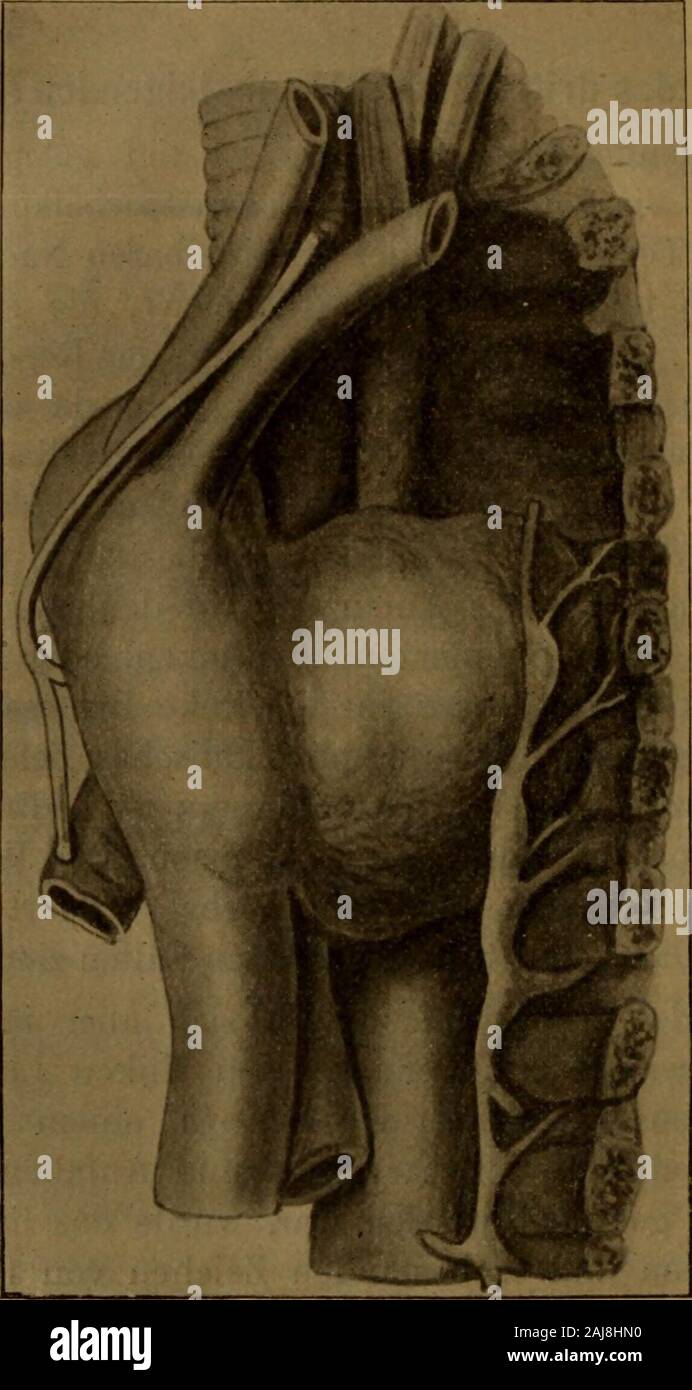

Grundriss der Lungenchirurgie . 5. Läge der Lungen und Trachea von hinten. Nach Paasch, Anat. Vorles., Fig. 43. Die mediastinalen Pleurablätter ziehen von der Rückseite desBrustbeines nach hinten zu beiden Seiten

Herzkrankheiten, mit besonderer Berücksichtigung der Prognose und der Therapie . klinisch unter dieser Be-zeichnung den Antheil der Aorta vom Perikard bis zum Ursprüngeder Anonyma zu verstehen. Die wichtigsten Nachbarorgane desaufsteigenden Theiles des